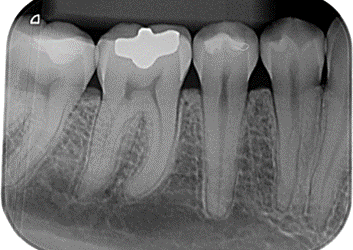

PERIAPICAL